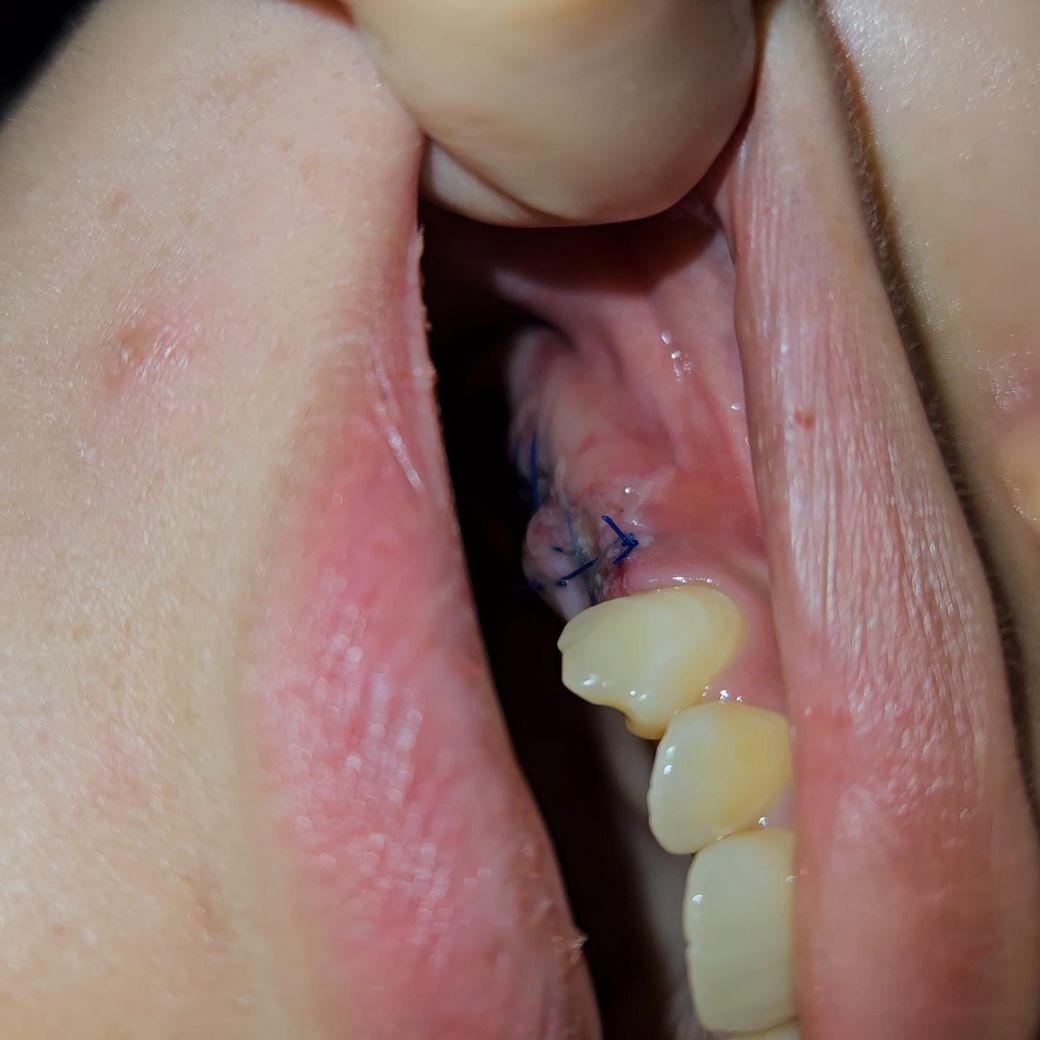

• 1번 째 사진

• 사진 보니 새살 올라 오는거 같기도 하고.. 염증같기도 하고...

사진상에 보이는건 잇몸이 치유되면서 생기는 자연스러운 현상이니 크게 걱정은 안하셔도 될것같습니다.

5월 20일 임플란트 심은 것은 정상적으로 아물고 있는 것으로 보입니다. 토요일 가 실밥 풀면 될 것으로 보입니다.

너무 불안해서 먼저 질문 글 드립니다 ㅠㅠ -> 사진으로 봤을때 염증의 양상은 아닙니다